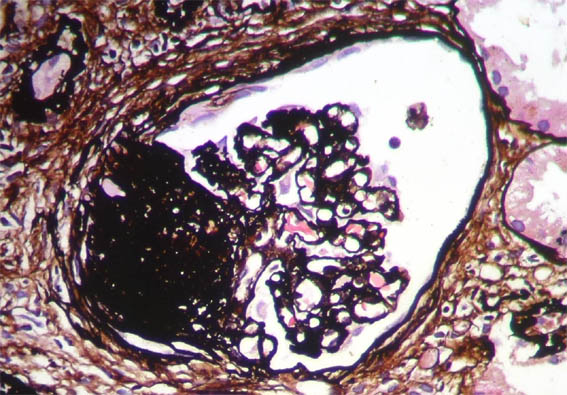

Figure 10. Methenamine-silver stain,

X400.